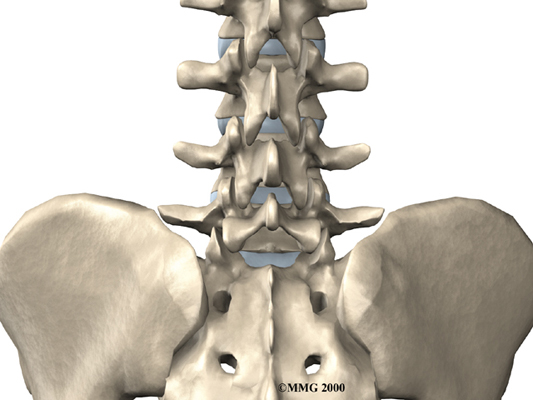

The human spine is formed by 24 spinal bones, called . Vertebrae are stacked on top of one another to form the spinal column. The spinal column gives the body its form. It is the body's main upright support. The section of the spine in the lower back is known as the .

The lumbar spine is made up of the lower five vertebrae. Doctors often refer to these vertebrae as L1 to L5. These five vertebrae line up to give the low back a slight inward curve. The lowest vertebra of the lumbar spine, L5, connects to the top of the sacrum, a triangular bone at the base of the spine that fits between the two pelvic bones. Some people have an extra, or sixth, lumbar vertebra. This condition doesn't usually cause any particular problems.